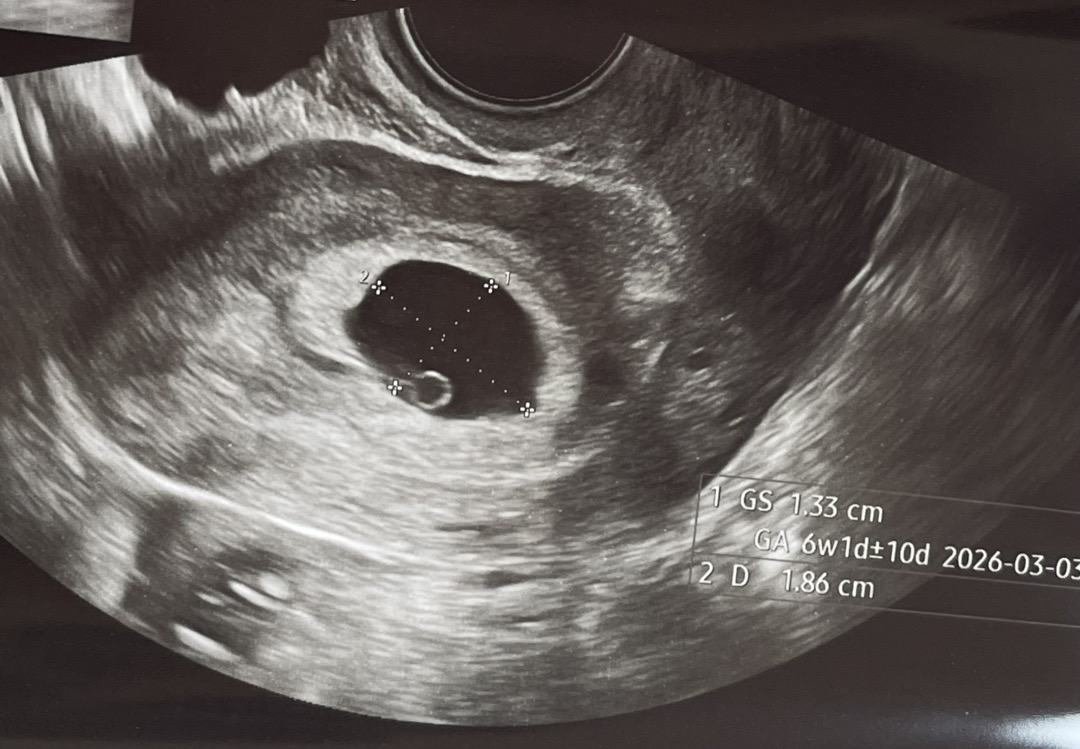

6주 3일인 줄 알고 지내다가 오늘 아기집 크기 재고 6주 1일로 정정되었네요 지난주 작은 아기집 처음 보고 일주일이 얼마나 길었는지…🥲 그새 아기집 잘 자라고 커뮤니티에서만 보던 난황까지 생겨서 너무 신기했어요 혼자 밥먹다가 괜히 눈물이 핑.. 고맙고 벅차는 기분이 드네요 한 열흘 후에 심장소리 들으러 가기로 했는데 또 이런저런 생각하며 지낼 거 같아요 이런저런 질문에 답변 달아주신 많은 베동님들 덕분에 잘 버텼어요🩵 초기인 분들 궁금한 거 물어보시면 아는 선에서 답해드릴게요 😙